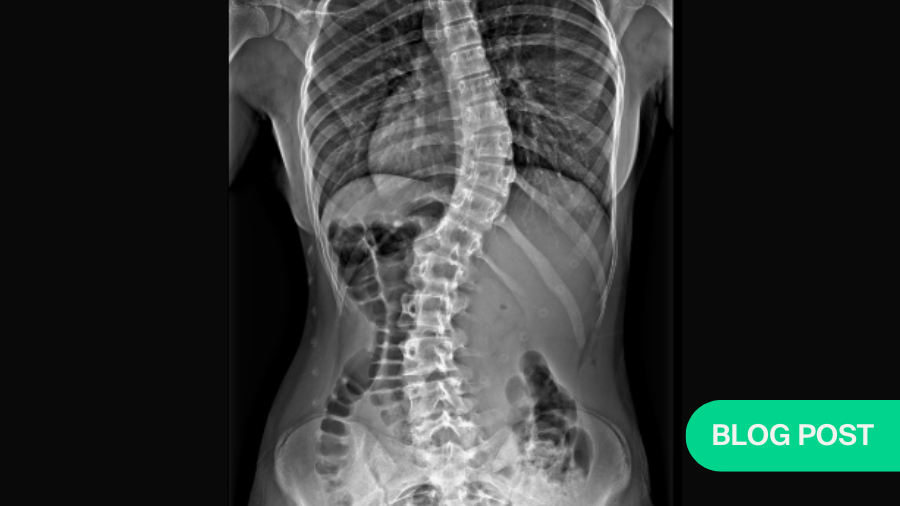

Scoliosis, a lateral curvature of the spine, affects many individuals, particularly adolescents. Adolescent Idiopathic Scoliosis (AIS) with no known cause is the most common form of scoliosis. Over the past 50 years, various exercises and physical therapy programs have been prescribed to manage this condition.